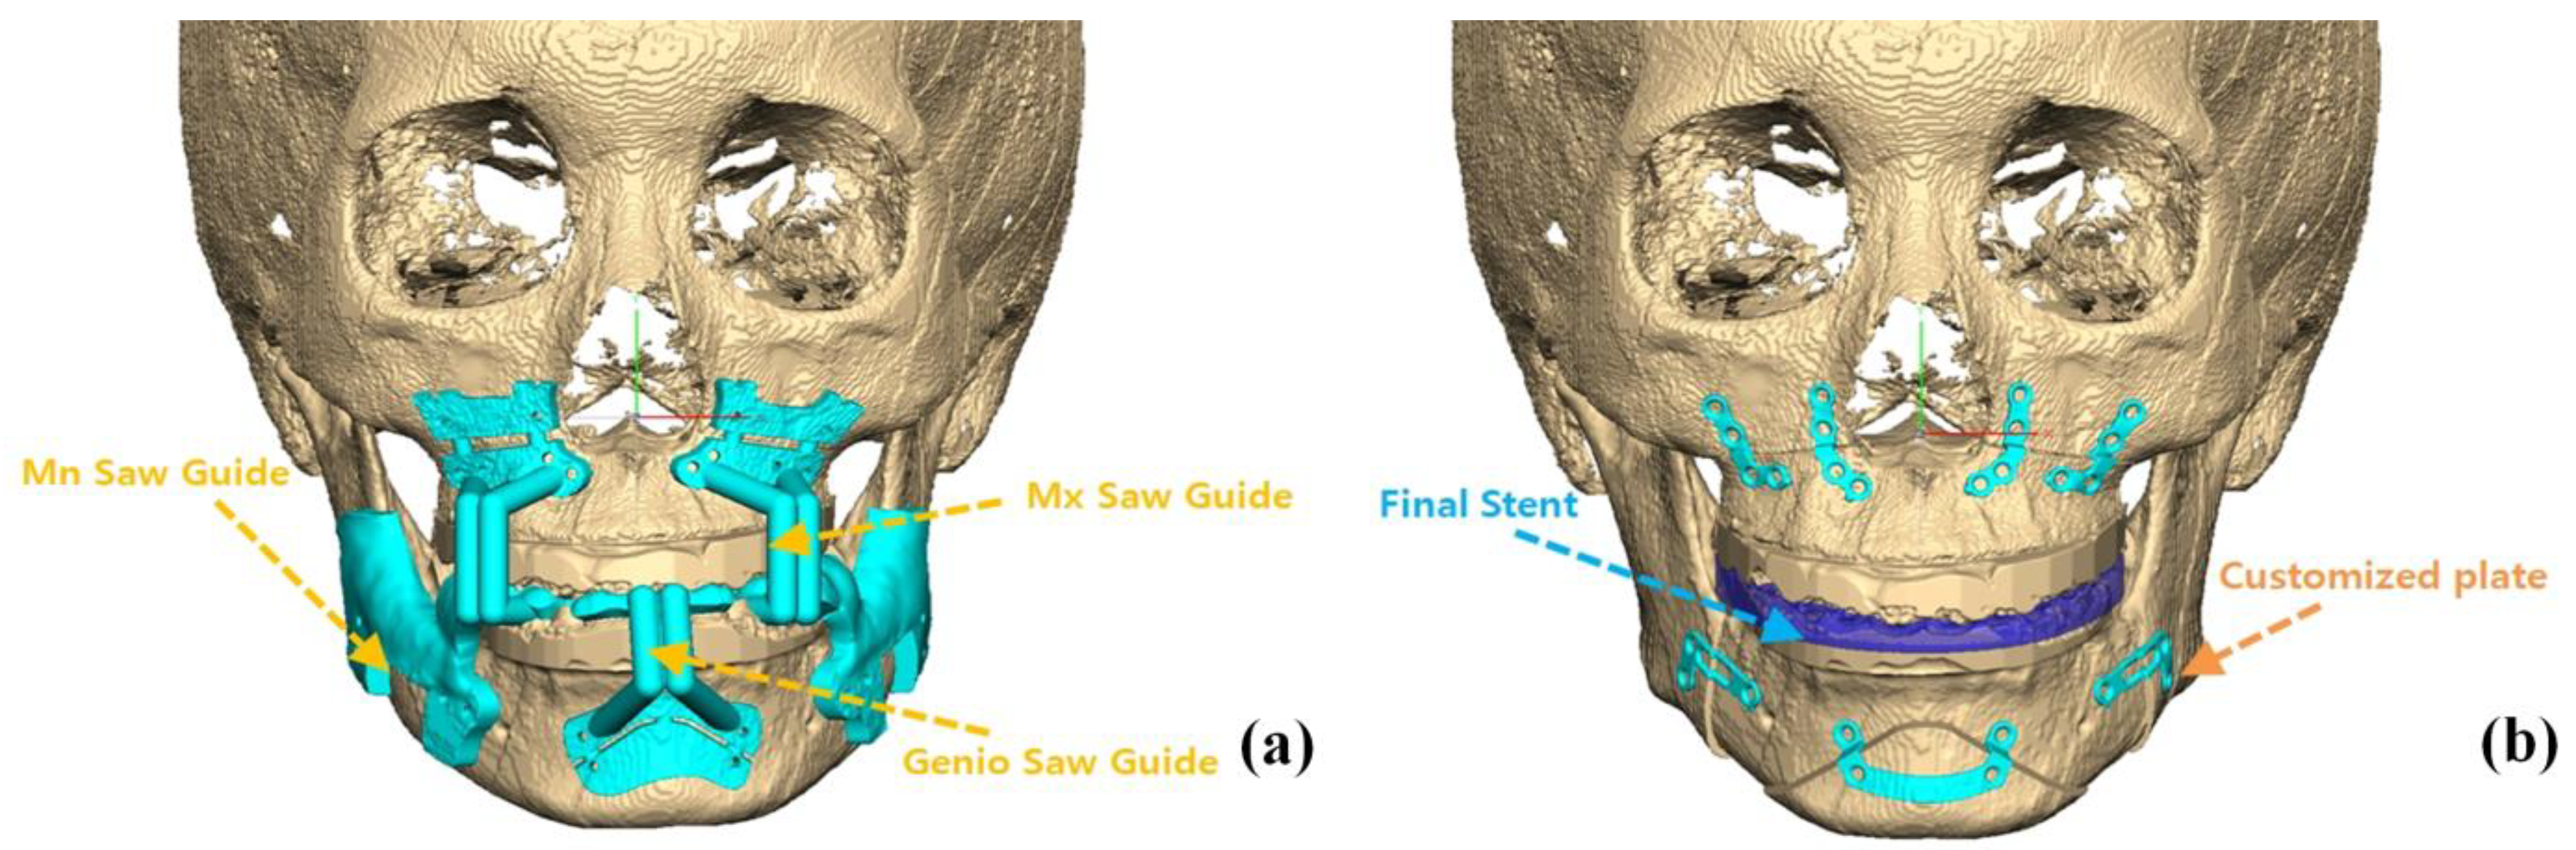

2.2. Treatment Protocols and CBCT Imaging

2.3. Condylar Volume Rendering